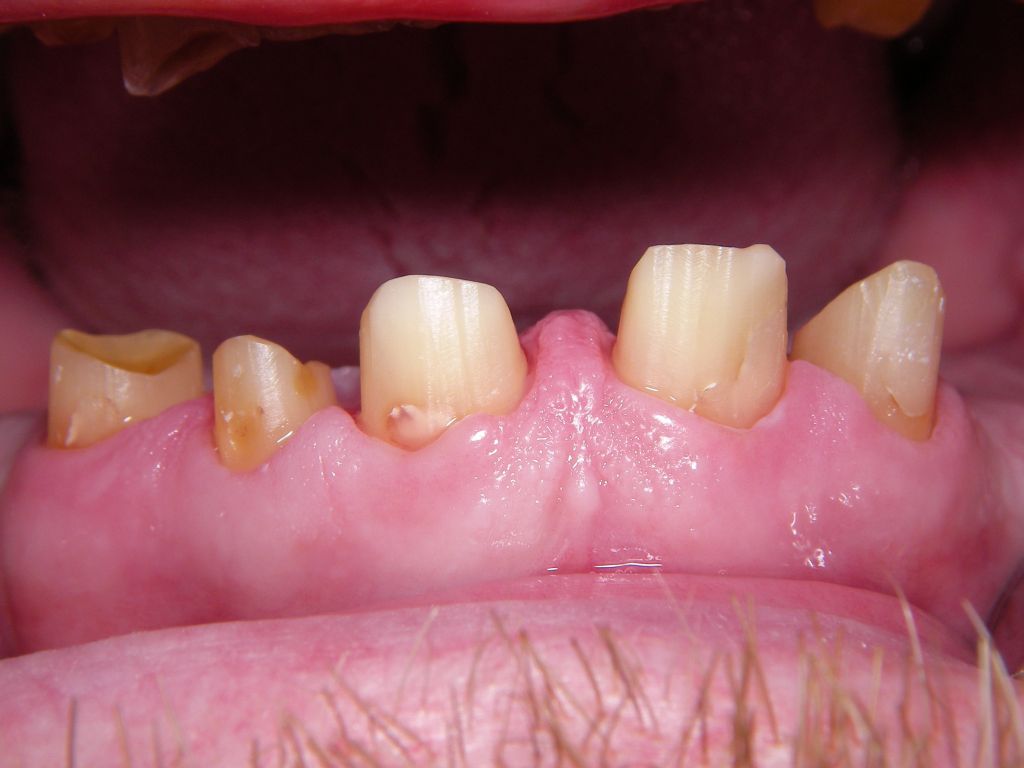

Das Hauptproblem dieses Falles lag im Oberkiefer - die über die Jahrzehnte abgeknirschten, kurzen Zähne erschweren Kronen, die durch eine Prothese belastet werden können. Die gewählte Lösung besteht darin, die Zähne nur rundherum zu beschleifen, aber nicht mehr zu kürzen und die Prothese mit einem Druckknopfsystem an die Zähne anzukoppeln, das ein "Spiel" aufweist, so daß die Prothese nicht als Hebelarm auf die schwachen Restzähne wirken kann. Rechts die beschliffenen Zähne kurz vorm Zementieren der Kronen.

Oberkieferrestzähne von vorne